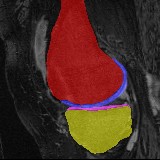

Moving Target Mono-0 Mono-5 DA-1 DA-5 Mono-200 Refer to caption Refer to caption Refer to caption Refer to caption Refer to caption Refer to caption Refer to caption Refer to caption Refer to caption Refer to caption Refer to caption Refer to caption Refer to caption Refer to caption

Figure 2:  Examples of knee MRI registration (top) and brain MRI segmentation (bottom) results. Top: The first two columns are the moving image/segmentation and the target image/segmentation followed by the warped moving images (with deformation grids)/segmentations by different models. Bottom left to right: original image, manual segmentation, and predictions of various models. Mono-i𝑖i and DA-i𝑖i represent the mono- and DA models with i𝑖i manual segmentations respectively.

Results: All trained networks are evaluated using Dice overlap scores between predictions and the manual segmentations for the segmentation network, or between the warped moving segmentations and the target segmentations for the registration network. Tabs. 1 and 2 show results for the knee and brain MRI experiments respectively in Dice scores (%). Fig. 2 shows examples of knee MRI registrations and brain MRI segmentations.

Qualitative results: DA achieves more anatomically consistent registrations than the mono-networks on the knee (Fig. 2) and Brain MRI samples (see supplementary material).

Image Manual Seg DA-1 Mono-5 DA-5 Mono-200 Refer to caption Refer to caption Refer to caption Refer to caption Refer to caption Refer to caption

Figure 4: Examples of brain MRI registration (top) and knee MRI segmentation (bottom) results. Top: The first two columns are the moving image/segmentation and the target image/segmentation followed by the warped moving images/segmentations by different models. Bottom left to right: original image, manual segmentation, and predictions of various models. Mono-i𝑖i and DA-i𝑖i represent the mono- and DA models trained with i𝑖i manual segmentations respectively.